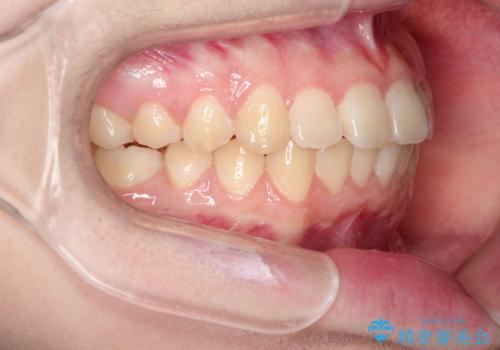

なるべく通院回数を減らして矯正したい インビザラインでのガタガタ矯正

- 10代女性

- インビザライン

- 1年2ヶ月

- 上下の歯並びを治したいとのことで来院されました。

受験生ということもあり、なるべく通院回数を減らしての矯正を希望されたので、インビザラインで治療をすることにしました。

ワイヤー矯正が1か月に1回程度来院が必要なのと比較すると、2-3か月に1回の来院でもよいので(症例によります)、通院回数を減らすことができて、患者様の負担を減らすことができます。